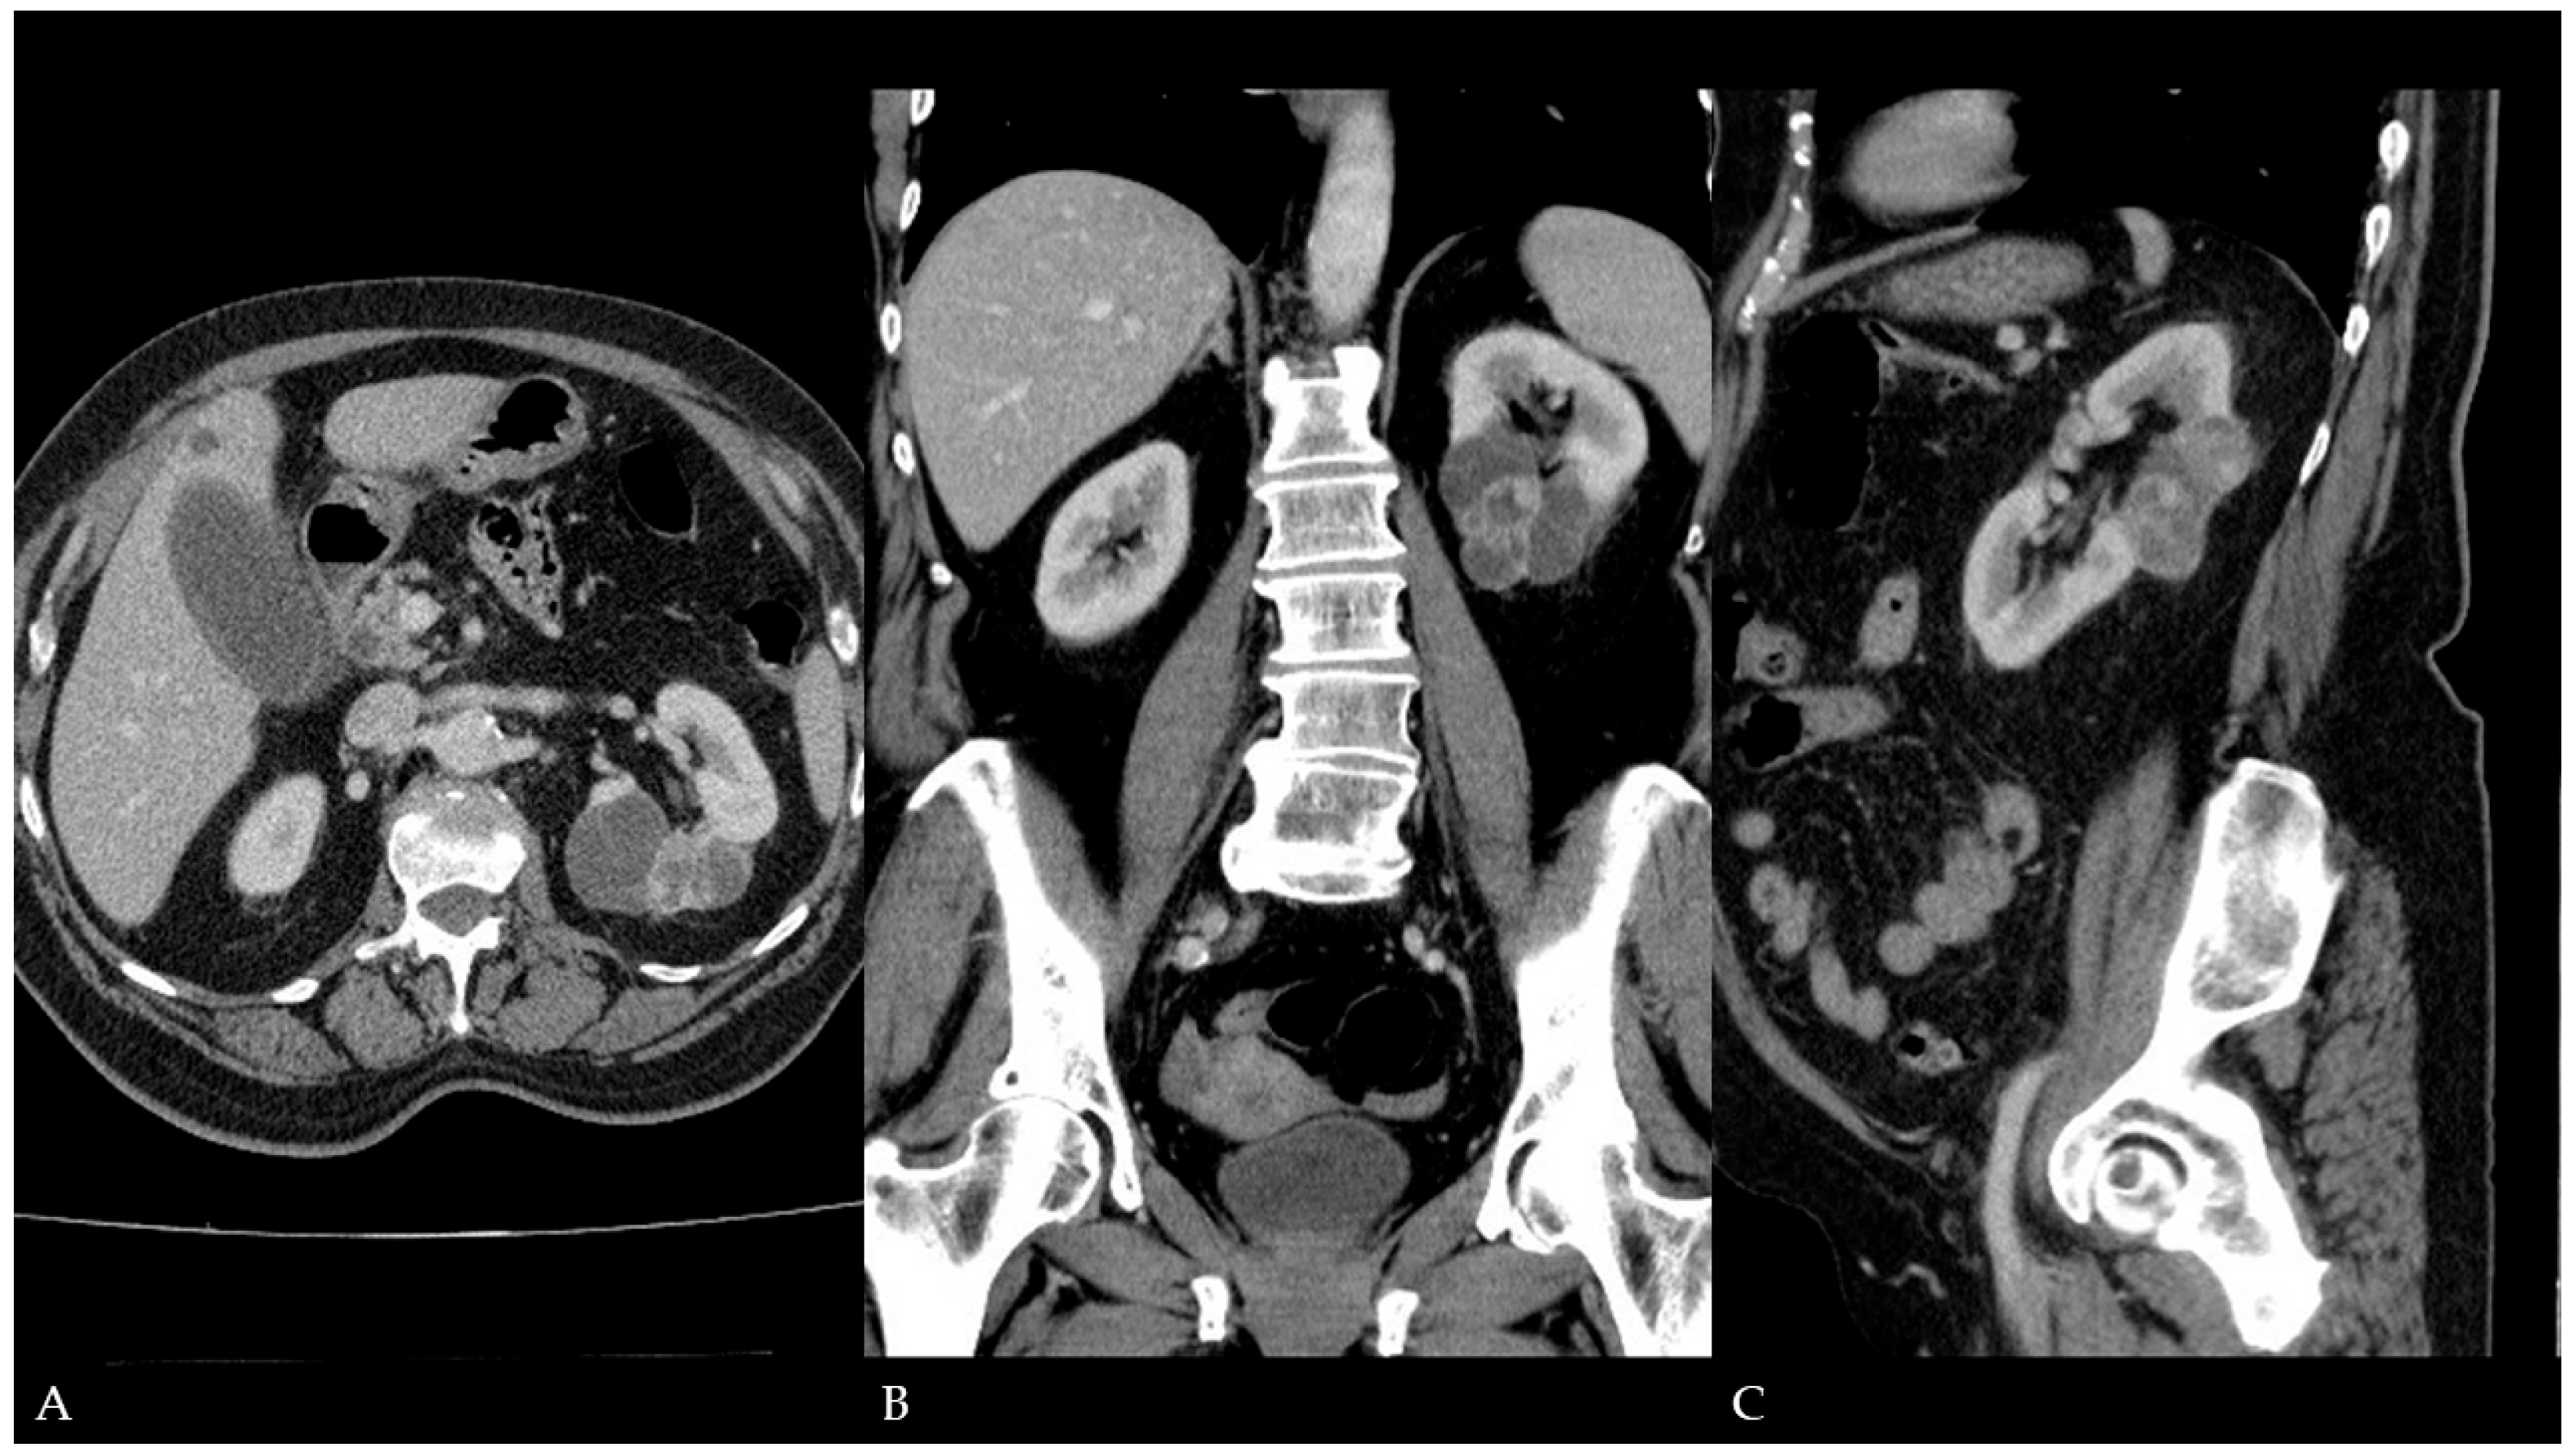

Malignant Transformation of Renal Cyst with Bosniak I Features

Ćulap, S.; Brkić, F.; Matković, A.; Svetec, J.; Jurjević, N.; Horvat Pavlov, K.; Vidjak, V.; Ferenc, T. Malignant Transformation of Renal Cyst with Bosniak I Features. Diagnostics 2025, 15, 1326. https://doi.org/10.3390/diagnostics15111326